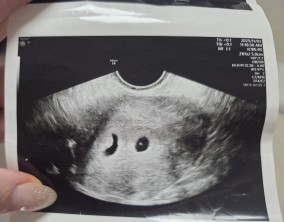

조금 느린 여정이었지만, 결국 도착한 두 줄

두 번의 기적을 안겨준 병원

인공수정 1차의 기적

시험관 1차, 진짜 로또가 찾아왔어요

첫째도, 둘째도 서울IVF에서 만난 기적